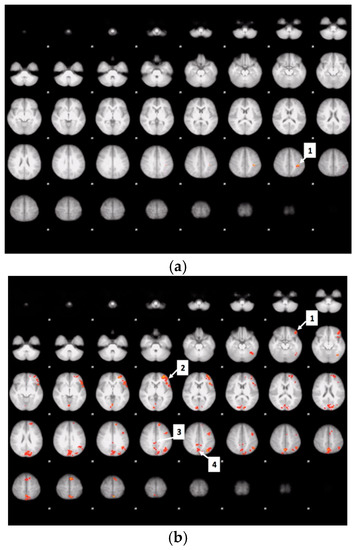

3.7. Drink Effects on Whole Brain Activity Associated with Food Valuation